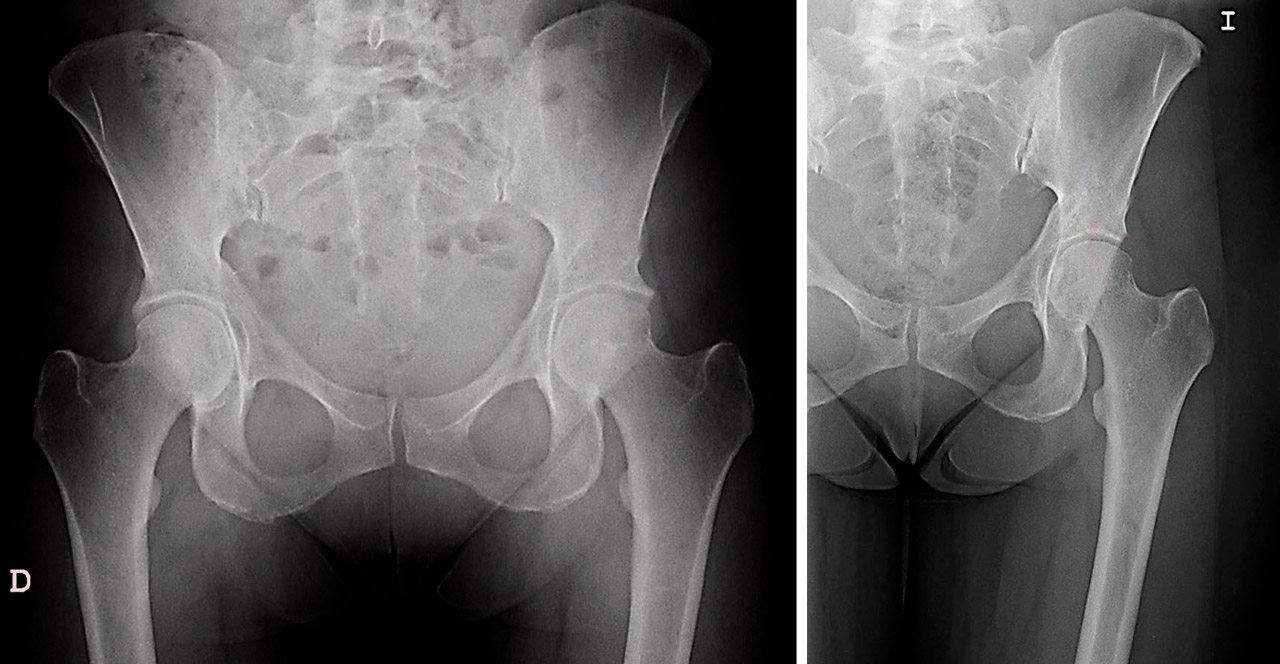

Para llevar a cabo la resección de las formas con exceso de cobertura, seguimos los conceptos de planificación propuestos por Matsuda(15). Así, dibujamos sobre la pantalla del intensificador el patrón de la zona de resección en la proyección anteroposterior (AP), como propugna Matsuda(15), pero también lo hacemos en la axial. Ello nos permite definir mejor la resección anteromedial y la superolateral. Iniciamos la resección de la zona superior y anterior de más fácil acceso, lo que además nos permitirá ir ampliando la resección. Dirigimos esta primero hacia la zona más anterior y medial, y después a la más lateral y posterior. Nos guiaremos en nuestra resección secuencial por las marcas realizadas sobre el intensificador hasta comprobar la normalización del ángulo de cobertura (zona superolateral) y conseguir la neutralización del signo de la pared posterior. Artroscópicamente, comprobamos la desaparición de los signos dinámicos de choque. La resección media realizada en estos casos es de unos 10 mm, como se ha publicado(15). Durante toda esta parte del procedimiento, mantendremos una tracción mínima, siendo suficiente evitar lesionar el cartílago de la cabeza femoral durante la acetabuloplastia de resección del PINCER. Una vez completada, aumentaremos la tracción e iniciaremos el tratamiento de las demás lesiones. En la Figura 2 podemos apreciar el resultado postoperatorio en relación con la valoración preoperatoria de este tipo de casos.